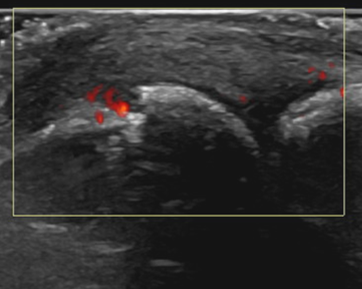

Der hochauflösende Ultraschall mit modernsten Geräten dient - ergänzend zur genauen Befragung (Anamnese) und der klinischen Untersuchung - zur Diagnose und gezielten ultraschallgesteuerten Punktion/Infiltration bei verschiedenen Erkrankungen des Bewegungsapparates.

Dabei lassen sich mittels Ultraschall strukturelle Schäden, akute Entzündungen oder sogar gestörte Bewegungsabläufe in der «dynamischen» Untersuchung darstellen. Aufgrund der ausgezeichneten Auflösung lassen sich mittlerweile auch kleinste Strukturen darstellen, punktieren und infiltrieren.